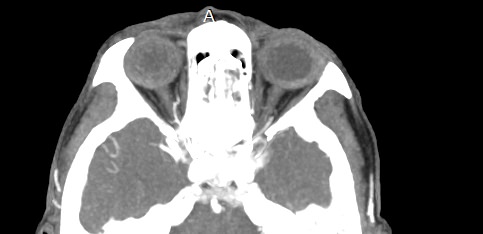

Орбиты (или глазницы) – это костные углубления в лицевом черепе, где расположены глазные яблоки, окруженные жировой клетчаткой, а также слезные железы, слезные каналы, сосуды, нервы, мышцы и связки глаза. Такая небольшая по объему область содержит важные анатомические структуры, обеспечивающие нормальную функцию органа зрения.

Кроме того, область орбиты тесно связана с близлежащими структурами – полостью черепа с расположенным в ней головным мозгом, а также с полостью носа, околоносовыми пазухами и носоглоткой. Различные патологические процессы могут развиваться как в самой глазнице, так и в околоорбитальных структурах, но при этом распространяться на область орбит.

Мультиспиральная компьютерная томография лучше всего визуализирует ткани с высокой плотностью, к которым, в частности, относится костная ткань. Это делает КТ незаменимой при диагностике травматических повреждений глазниц, а также для выявления инородных тел орбит.

На снимках КТ хорошо видны костные структуры глазниц, глазные яблоки, ретробульбарная клетчатка, слезные железы, канальцы, слезные мешки, носослезные каналы.